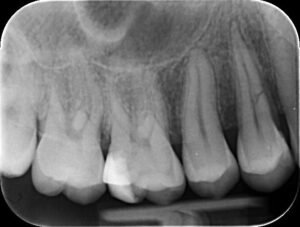

Stap 1: extractie en herstel

Door de actieve ontsteking en het aanzienlijke botverlies kon het implantaat niet direct geplaatst worden na het trekken van de beschadigde tand. Eerst moest de ontsteking rustig worden en het tandvlees herstellen. Als tijdelijke, esthetische oplossing plaatsten we de kroon van zijn eigen tand — na het verwijderen van de wortel — tussen zijn andere tanden. Zo kon de patiënt meteen normaal functioneren tijdens de genezingsperiode.

Stap 2: plaatsing van het implantaat en botopbouw

Zodra het mondslijmvlies rustig was en de mondgezondheid weer hersteld, konden we het implantaat plaatsen. Tegelijkertijd voerden we een botopbouw uit: door de ontsteking was kaakbot verloren gegaan en een stevig fundament is cruciaal voor stabiliteit. We vulden het ontbrekende bot aan zodat het implantaat goed omringd wordt en een solide basis krijgt.